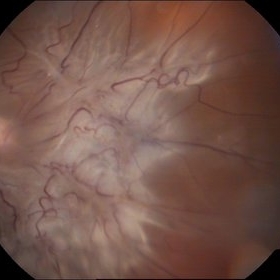

Rerinal Detachment with PVR

Sep 10 2014 by Mehul A Shah

A myopic male patient 35-years-old presented to outdoor and found to have retinal detachment with multiple fixed folds.

Photographer: Drashti Netralaya,Dahod

Imaging device: FF 450

Condition/keywords: proliferative vitreoretinopathy (PVR)